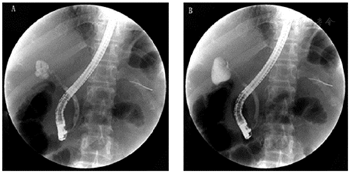

实验室AST: 114 U/L,ALT: 205 U/L,TBIL:141.10μmol/L, DBIL: 125.20μmol/L, IBIL:15.9μmol/L。AFP、CEA、CA125、CA199等肿瘤标志物均正常。腹部超声提示肝内及肝外胆管扩张。CT示胆总管下段占位性病变(图1)。MRCP提示胆总管中段局限性狭窄并肝内外胆管及胆总管上段扩张,不支持典型肿瘤性病变(图2)。ERCP提示胆总管远端正常,导丝无法通过胆总管下段(图3)。